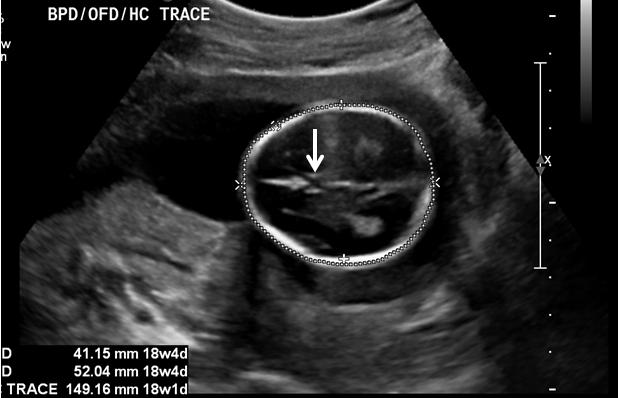

At what level is the BPD and HC taken?

the level of the thalami

What is the formula for HC?

(BPD + OFD)(Pie)/2

How is the HC measurement taken?

outer to outer

Why is the HC a valuable measurement?

less affected by head compression